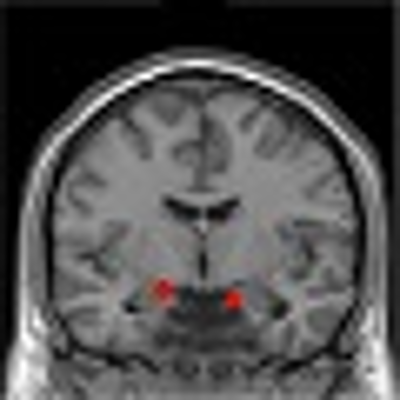

Post-traumatic stress disorder (PTSD) can develop after exposure to a potentially traumatic event that is beyond a typical stressor. Events that may lead to PTSD include, but are not limited to, violent personal assaults, natural or human-caused disasters, accidents, combat, and other forms of violence. Exposure to events like these is common. About one half of all U.S. adults will experience at least one traumatic event in...